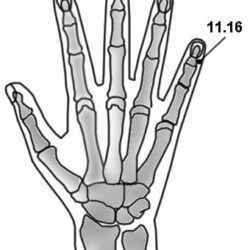

מיקום שתי נקודות, בחלק המדיאלי של האצבע המורה, על הצד הפלמרי של קו ה- D, הנקודות צמודות למפרק המטא פלנגיאלי. Dr Li Guo Zheng: יש שלוש נקודות באזור הזה. שם הנקודה Mù 木 – עץ. דיקור 0.3 – 0.2 צון קרוב לעצם. במחלות עור של הידיים דוקרים את הנקודה בצד של המחלה, למחלות האחרות דוקרים […]